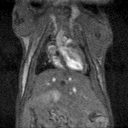

Ex vivo imaging can produce high-resolution images of the rat brain providing excellent delineation of brain regions. Image Credit: Scintica Instrumentation Inc

Ex vivo imaging of liver, allowing lesions to be identified, counted and measured (volume) as well as guide tissue sectioning for conventional pathological examination. Image Credit: Scintica Instrumentation Inc

Ex vivo imaging

Excised tissues preserved in formalin can undergo MRI at a resolution far higher than a live animal's. Ex-vivo 3D MRI makes identifying and measuring lesions in entire organs or brain structures possible. It can also assist in directing additional histopathological processing and sectioning for standard pathological analysis of areas of interest.